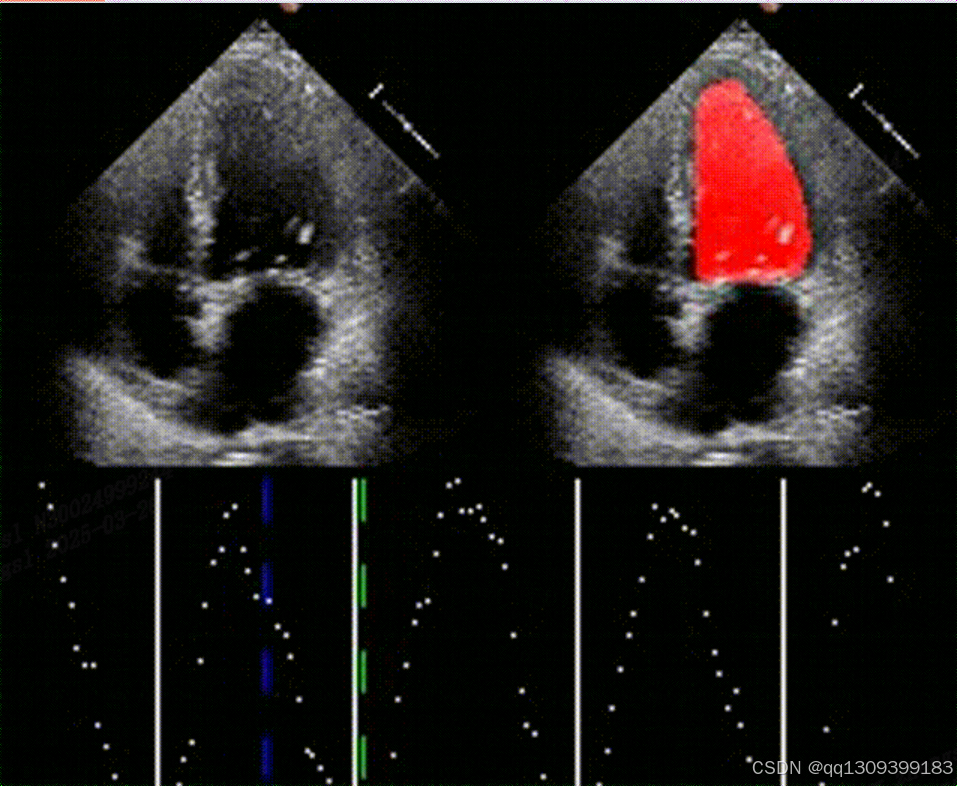

- 可视化验证:分割结果清晰勾勒左心室内膜边界(见图1),且在低信噪比帧中仍保持稳定性。